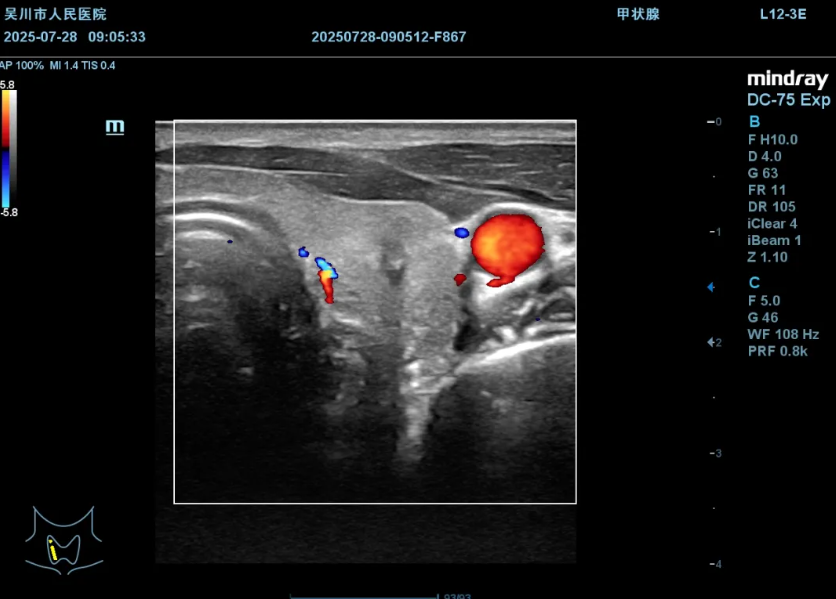

打好隔离带保护周围神经和血管

超声引导下消融针精准穿刺至结节内部

启动消融,通过高温灭活结节,实时观察结节逐渐气化